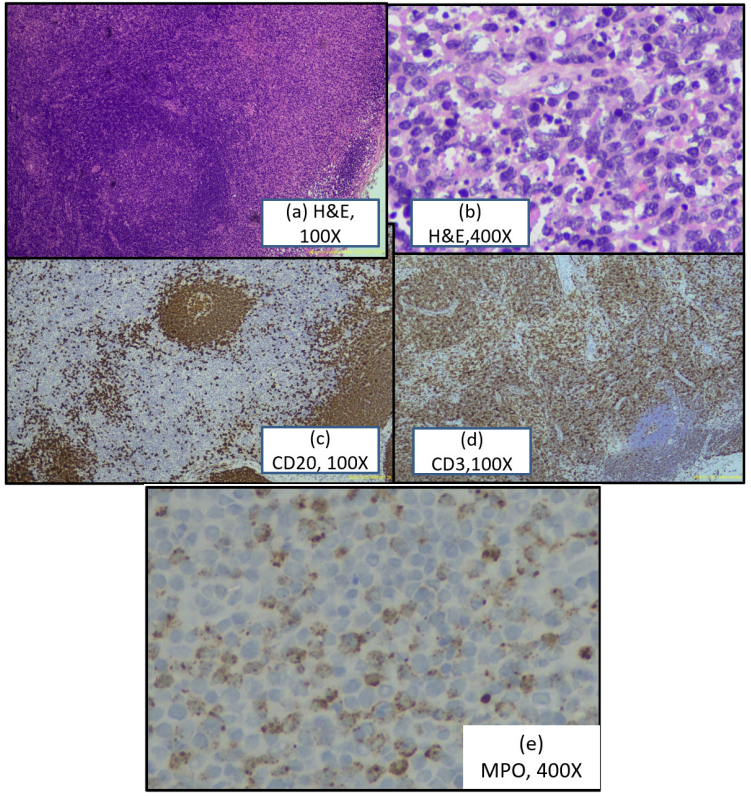

Histopathology (H&E Staining): Lymph node with effaced architecture. Atypical cells arranged in sheets displaying: Moderate eosinophilic cytoplasm, large nuclei with convoluted nuclear membranes (histiocytic morphology), Multiple foci of karyorrhectic debris (hallmark finding), Prominent areas of hyalinization, Remnant B-cell follicles partially preserved. Impression: Atypical lymphohistiocytic proliferation; recommend IHC.

Immunohistochemistry (Medium Panel)—Diagnostic Pattern:

CD3 (Clone MRQ-39): Diffuse positive staining, predominantly in interfollicular and paracortical regions

CD20 (Clone L26): Highlights remnant follicles only; negative in necrotic areas

CD30 (Clone BER-H2): Scattered positive cells (not extensive)

Myeloperoxidase (MPO): Scattered positive in histiocytes, reflecting myeloid origin

Diagnosis: Features favor Kikuchi-Fujimoto disease. The CD3+/CD20- pattern with paracortical necrosis, karyorrhectic debris, and MPO+ histiocytes established diagnosis. Differential considerations of autoimmune disease-associated lymphadenitis were excluded.

(a): H&E microphotograph showing effaced lymph node architecture with preserved follicles and prominence of histiocytes.

(b): H&E microphotograph showing foci of karyorrhectic debri.

(c):Immunohistochemistry showing CD20 positive follicles

(d): Immunohistochemistry showing CD3 positive in interfollicular region.

(e): Immunohistochemistry showing MPO expression in histiocytes

The characteristic histology—paracortical necrosis with abundant karyorrhectic debris—directly correlates with the disease's fundamental pathophysiology: apoptosis of infiltrating lymphocytes. The immunohistochemical pattern (CD3+/CD20-) indicates T-cell-mediated disease with sparing of B-cell follicles, consistent with current understanding of KFD as a CD8+ T-cell-driven condition.